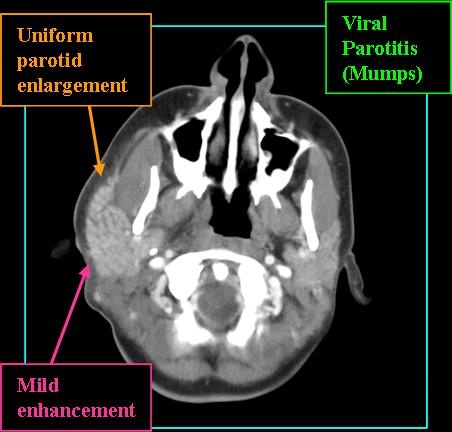

Radiologic Findings

- Gland should be diffusely and uniformly enlarged

- Contrast-enhanced CT of bacterial parotitis will show enhancing gland with subcutaeous fat-stranding

- MR signal high on T2 and post-contrast T1 shows gland enhancement